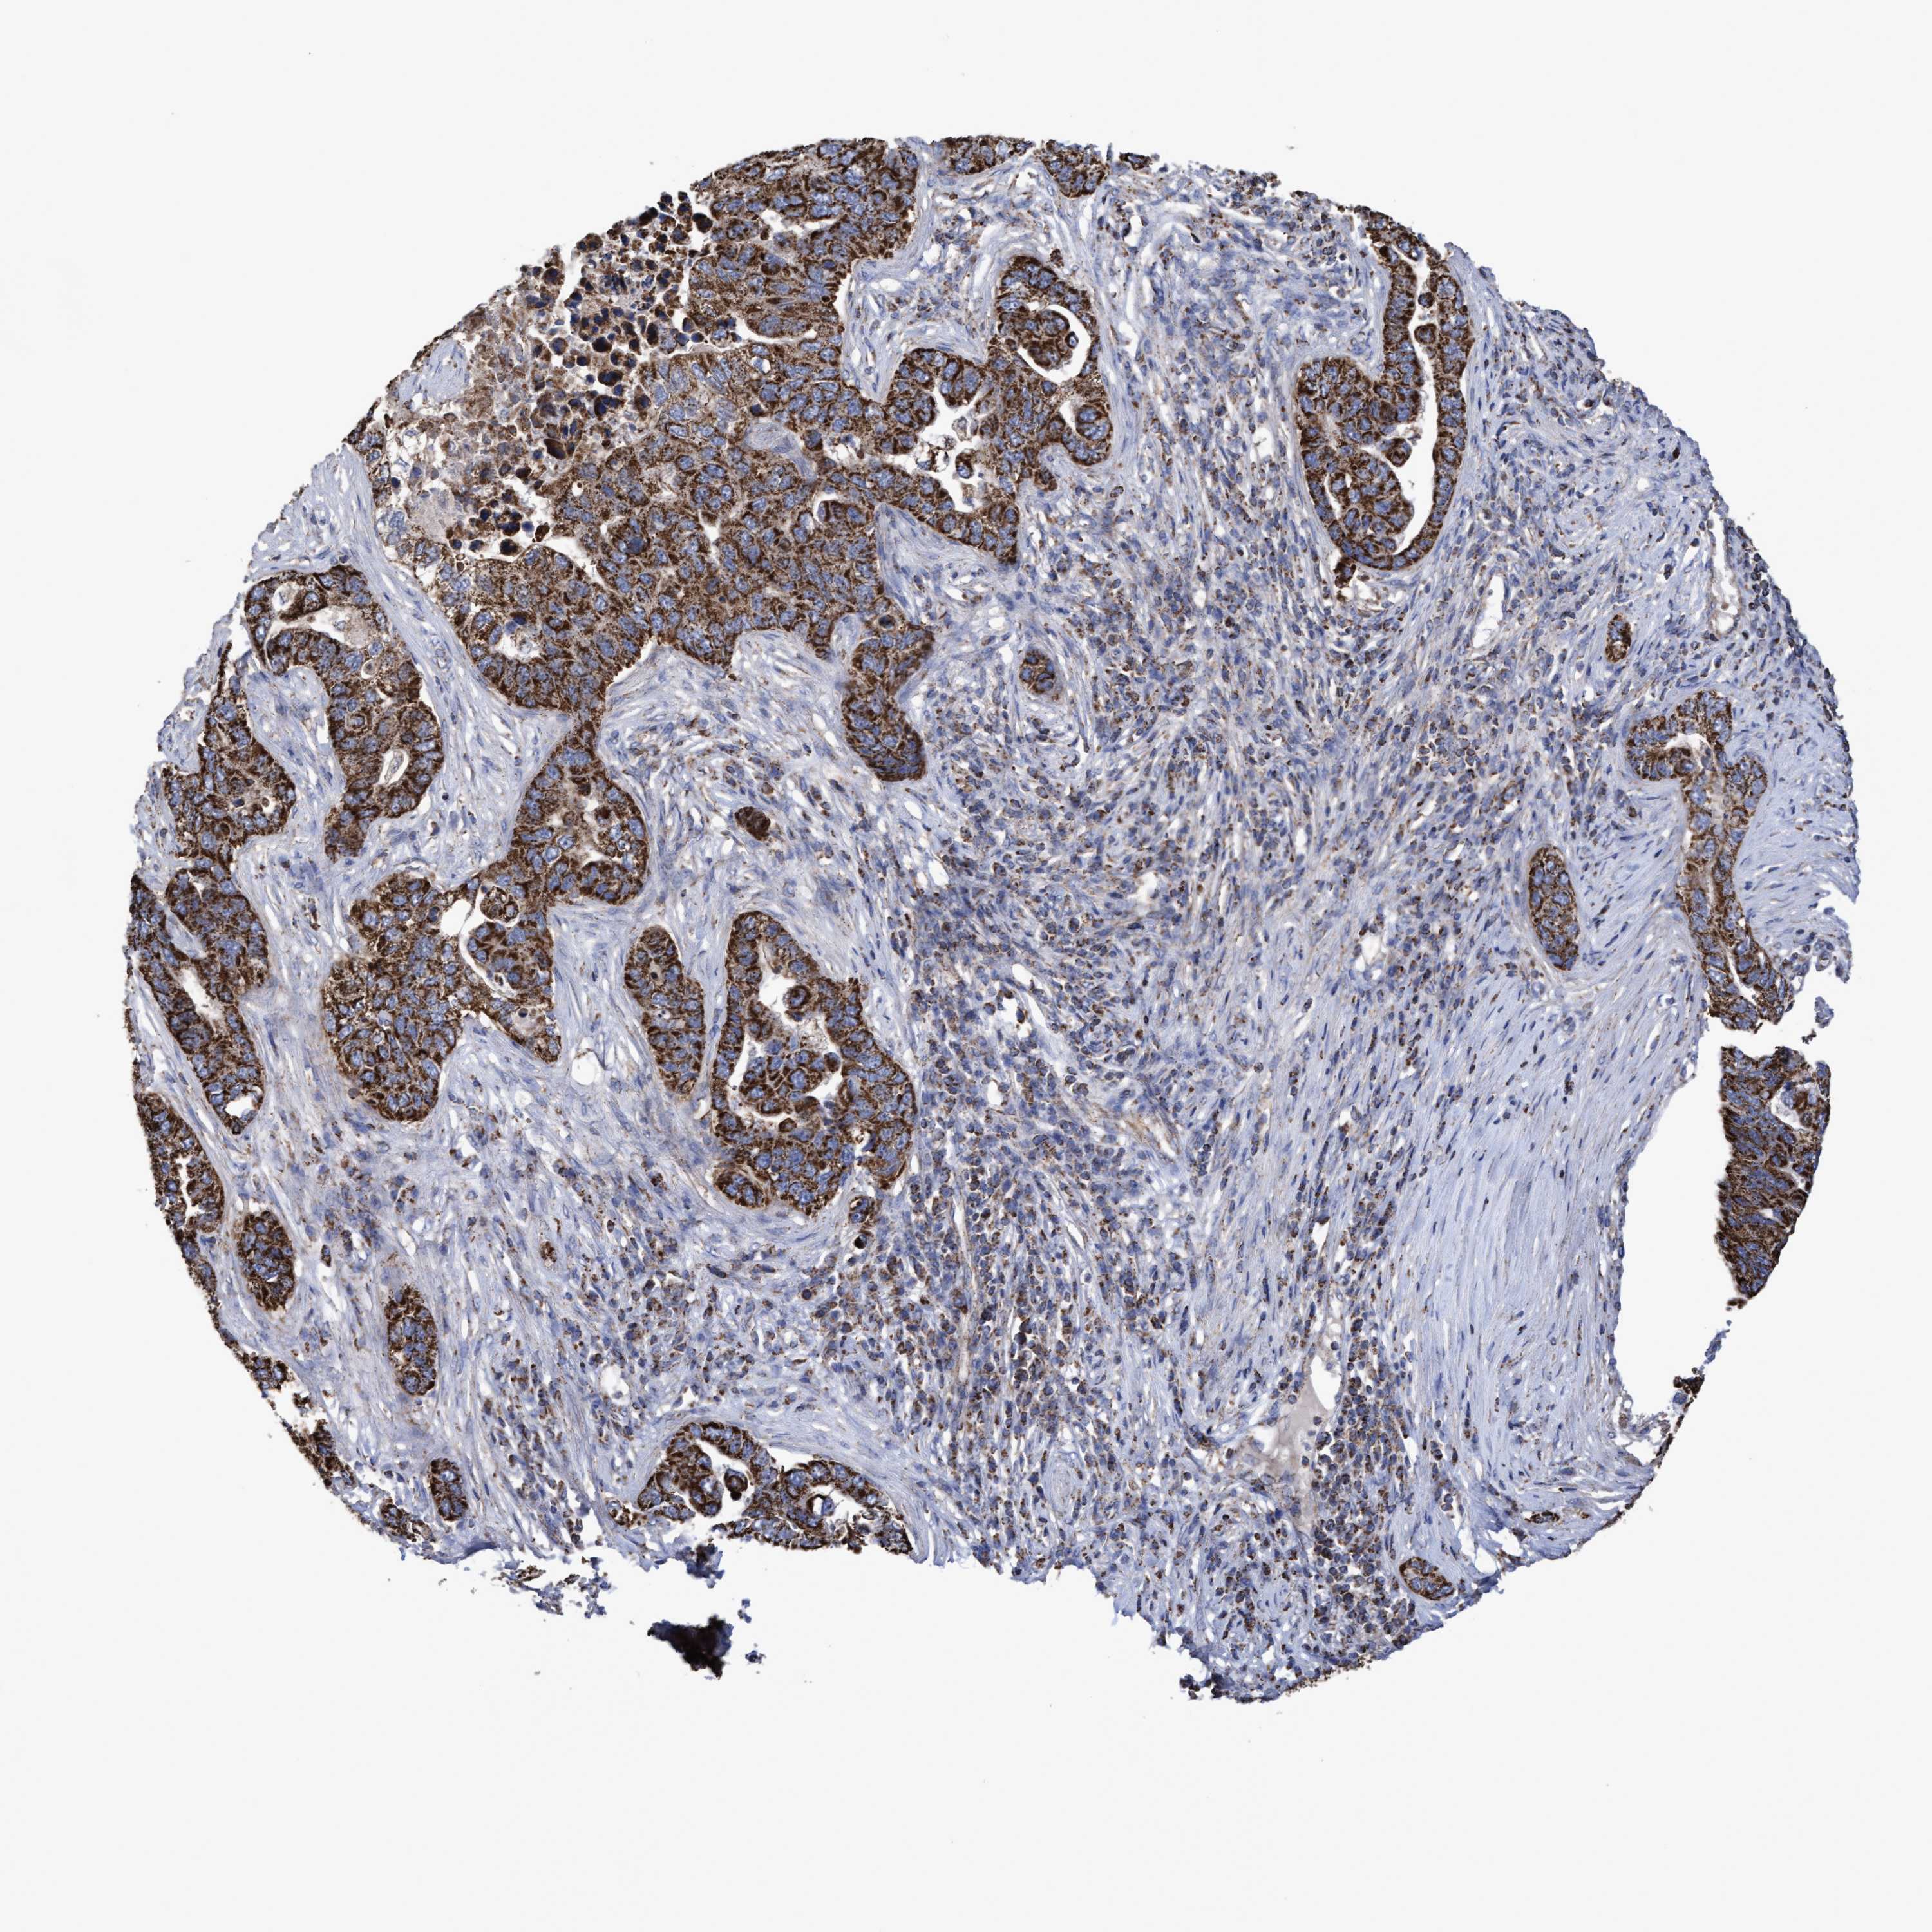

PANCREATIC CANCER - Protein expressioni

A mouse-over function shows sample information and annotation data. Click on an image to view it in a full screen mode. Samples can be filtered based on level of antibody staining by selecting one or several of the following categories: high, medium, low and not detected. The assay and annotation is described here.

Note that samples used for immunohistochemistry by the Human Protein Atlas do not correspond to samples in the TCGA dataset.

Antibody stainingi

Antibody staining in the annotated cell types in the current human tissue is reported as not detected, low, medium, or high, based on conventional immunohistochemistry profiling in selected tissues. This score is based on the combination of the staining intensity and fraction of stained cells.

Each image is clickable and will lead to virtual microscopy that enables deeper exploration of all samples and also displays staining intensity scores, fraction scores and subcellular localization as well as patient and tissue information for each sample.

Antibody HPA019033

Antibody HPA019167

Staining

High

Medium

Low

Not detected

Intensity

Strong

Moderate

Weak

Negative

Quantity

>75%

75%-25%

<25%

None

Location

Nuclear

Cytoplasmic/membranous

Cytoplasmic/membranous,nuclear

Adenocarcinoma, NOS